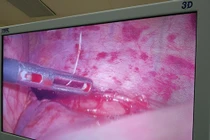

Bệnh nhân sau đó được chuyển vào Khoa Gây mê - Hồi sức. Với sự phối hợp nhịp nhàng của đội ngũ y bác sĩ, ca phẫu thuật nội soi ống cứng đã diễn ra thành công, lấy ra dị vật là cung răng giả sắc nhọn.

Ca nội soi kéo dài khoảng 40 phút, dị vật được lấy ra có kích thước 3x5cm. Do cấu tạo của hàm răng giả có nhiều mấu, bám chặt vào thực quản, gây khó khăn hơn so với các dị vật thông thường khác.